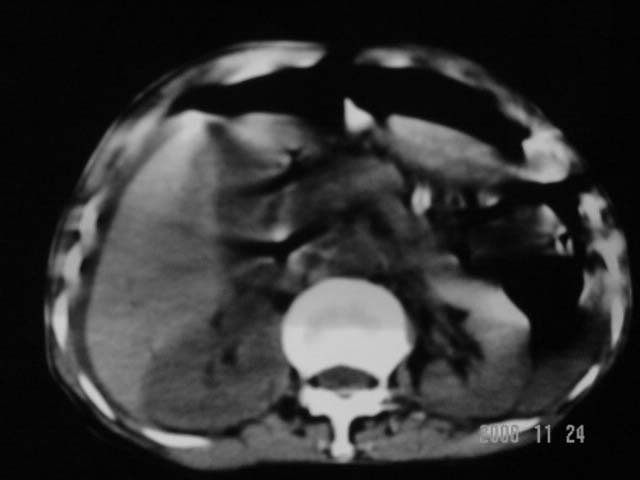

仰卧位见:肝前间隙及肝脾间隙内可见新月形气体密度影,边缘清楚,侧卧位见气体随体位改变而移动,ct值约-929hu。膈下、肝下间隙及部分肠间隙可见液性密度影。考虑:1、上腹部空腔脏器穿孔,以胃穿孔可能性大。2、少量腹水。

仰卧位见:肝前间隙及肝脾间隙内可见新月形气体密度影,边缘清楚,侧卧位见气体随体位改变而移动,ct值约-929hu。膈下、肝下间隙及部分肠间隙可见液性密度影。考虑:1、上腹部空腔脏器穿孔,结合临床,首先考虑胃穿孔可能性大。2、少量腹水

补充--肝门及肝肾间隙以见积气显示。

支持消化道空腔脏器穿孔(腹腔内大量游离气体影,小网膜囊内亦见气体影),少量腹水。